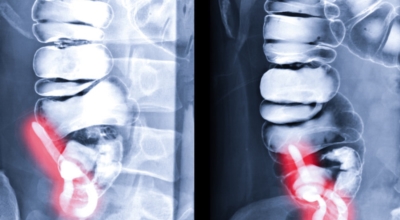

맹장염의 통증은 90%이상이 오른쪽 아랫배 부위에서 일어나며 처음에는 배꼽주변에서부터 통증을 느끼기 시작하다가 아랫배쪽으로 옮겨가기 시작합니다. 맹장염은 일반 복통과는 다르게 오른쪽 아래 부위에서 다리나 배쪽으로 점점 고통의 범위가 확장한다는 개성이 있고 또 하나의 포인트로는 맹장염은 기침이나 재채기가 나오기도하며 차에서 멀미를 할때의 묘한 불쾌감도 느껴지기도 합니다.

복통은 맹장염으로 나타나는 대표적인 증상으로 95% 이상이 극심한 복통을 겪게 돼요. 배꼽 주변에서 가벼운 통증을 느끼다가 점차 오른쪽 하복부까지 내려오면서 심한 통증을 느끼게 되는데, 허리를 곧게 펴지 못할 만큼 지속적인 통증이 생겨나게 됩니다. 또한 허리 아래쪽이나 골반에서 통증이 유발되기도 하며 경련 및 설사 복통이 천천히 나타나기도 그러나, 사람마다 충수 위치가 다를 수 있어 통증이 나타나는 위치는 조금씩 다를 수 있다고 합니다.